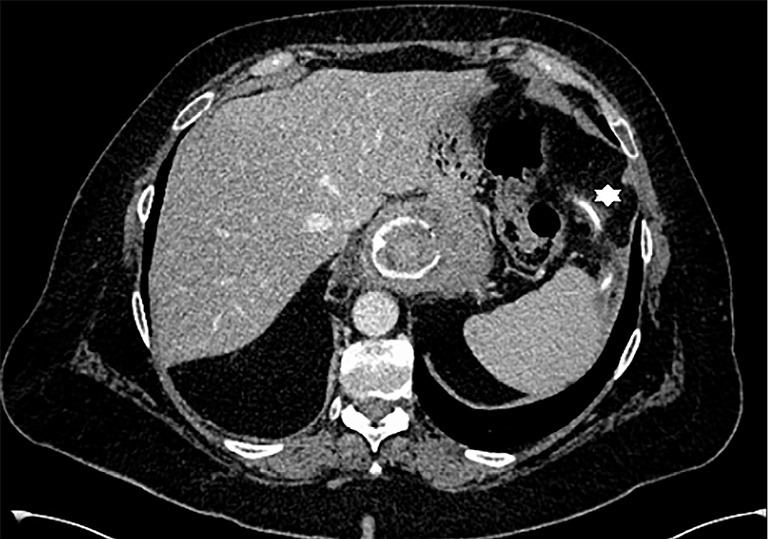

Case description: In our present case, we report on an asymptomatic patient with intraluminal penetration of the dislodged adjustment tube into the colon 26 years after implantation of a gastric banding system. We revealed the complication randomly by positron emission tomography-computed tomography (PET-CT) in the course of a tumor staging of a newly diagnosed lung cancer. The gastric band was removed laparoscopically, the adjustment tube however, had to be cut through due to extended adhesions and could only partially be removed. The rest of the catheter passed spontaneously via rectum on the following day.